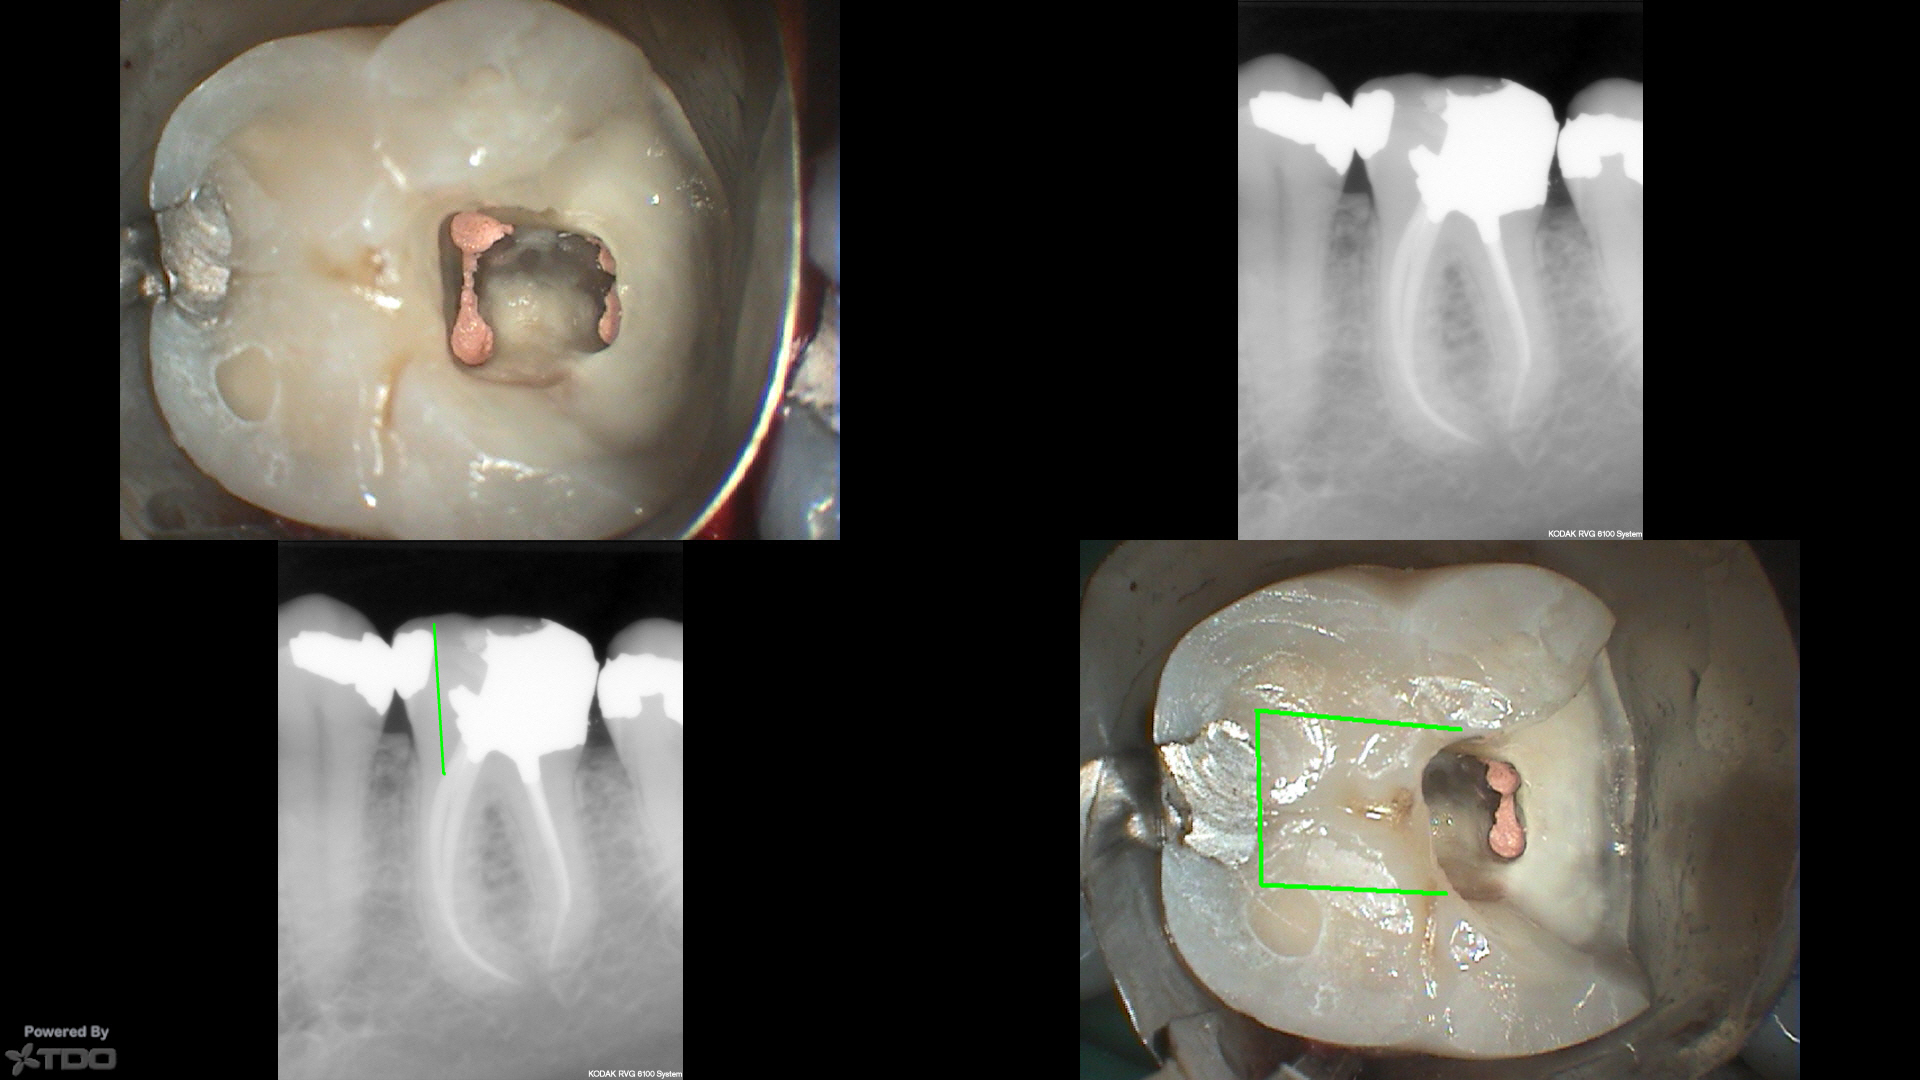

This patient was in yesterday for a different tooth, and we can see the pulp horn to the mesial along with drawings showing traditional SLA and how much tooth structure might have been left.

This was also a deep finish line case where my advice (to a new clinician in town) to leave the distal finish line on amalgam was not heeded. Ferrule only counts if the crown fits. Here…it doesn't seem to have mattered although I don't think anyone would be happy about that process outcome. I don't think it should be revised either, as there isn't any evidence that even the process outcome would be improved by such a revision.

Hi JK, totally unrelated question to the RCT, what matrix is that, just a regular tofflemire? Nice to see you at IAE, hopefully you remember beyond the tequila lol!

That is an automatrix.

https://www.safcodental.com/catalog/matrix-materials/matrix-systems/automatrix?ref=goadw&gclid=EAIaIQobChMIx-6t7cDM3AIVHZ7ACh0s_AoNEAAYASAAEgIVgvD_BwE